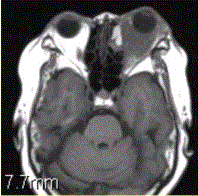

患者女,64岁,左眼突出5年余。查体左眼球前突6mm,眼球运动自如,眼底无异常,下睑扪及边界不清、质软的肿块,视力正常,MR表现如下图。临床拟...

问题 患者女,64岁,左眼突出5年余。查体左眼球前突6mm,眼球运动自如,眼底无异常,下睑扪及边界不清、质软的肿块,视力正常,MR表现如下图。 临床拟诊为

选项 A.眶内炎性假瘤 B.眼型Grave病 C.黑色素瘤 D.转移瘤 E.眼眶海绵状血管瘤 F.弥漫型淋巴管瘤

答案 A

解析 A